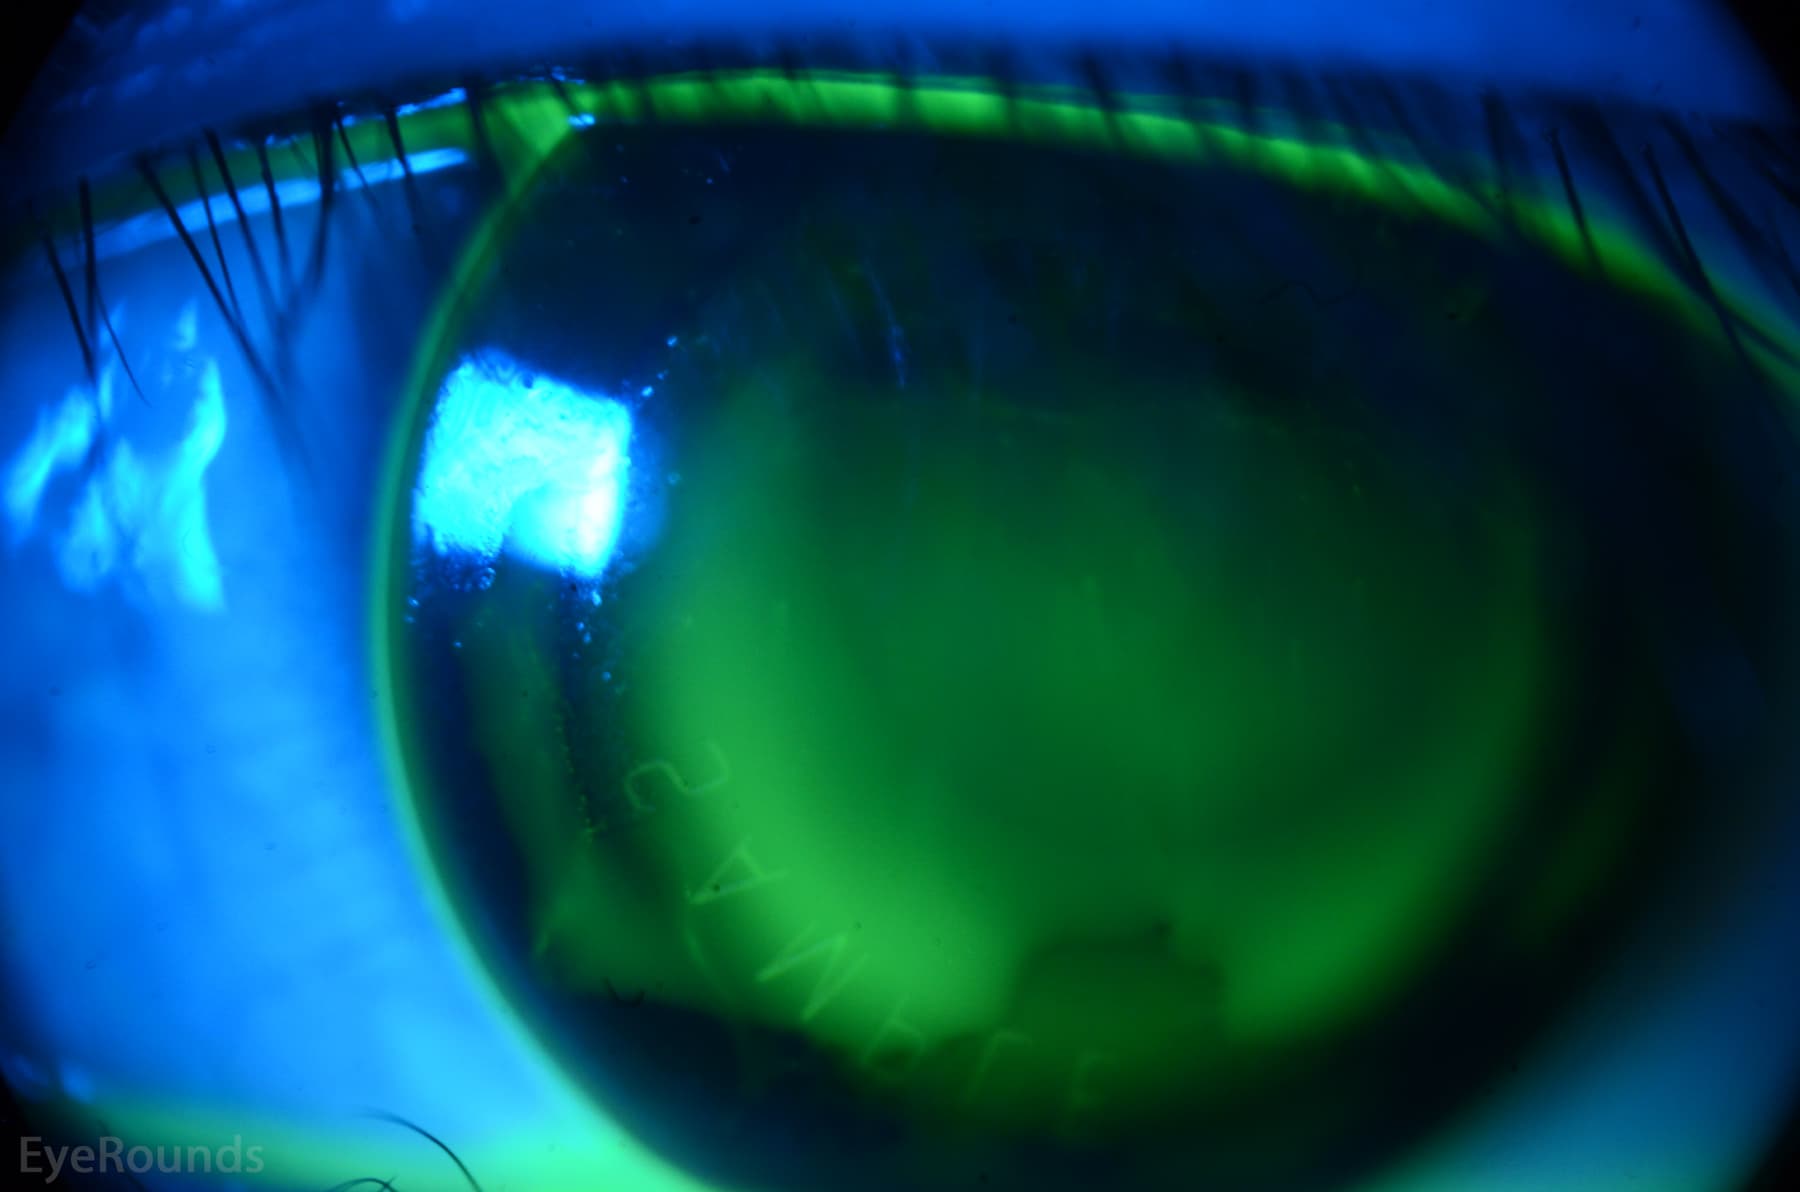

Clinical Images

High-resolution clinical photographs showing various presentations of myopia (nearsightedness).